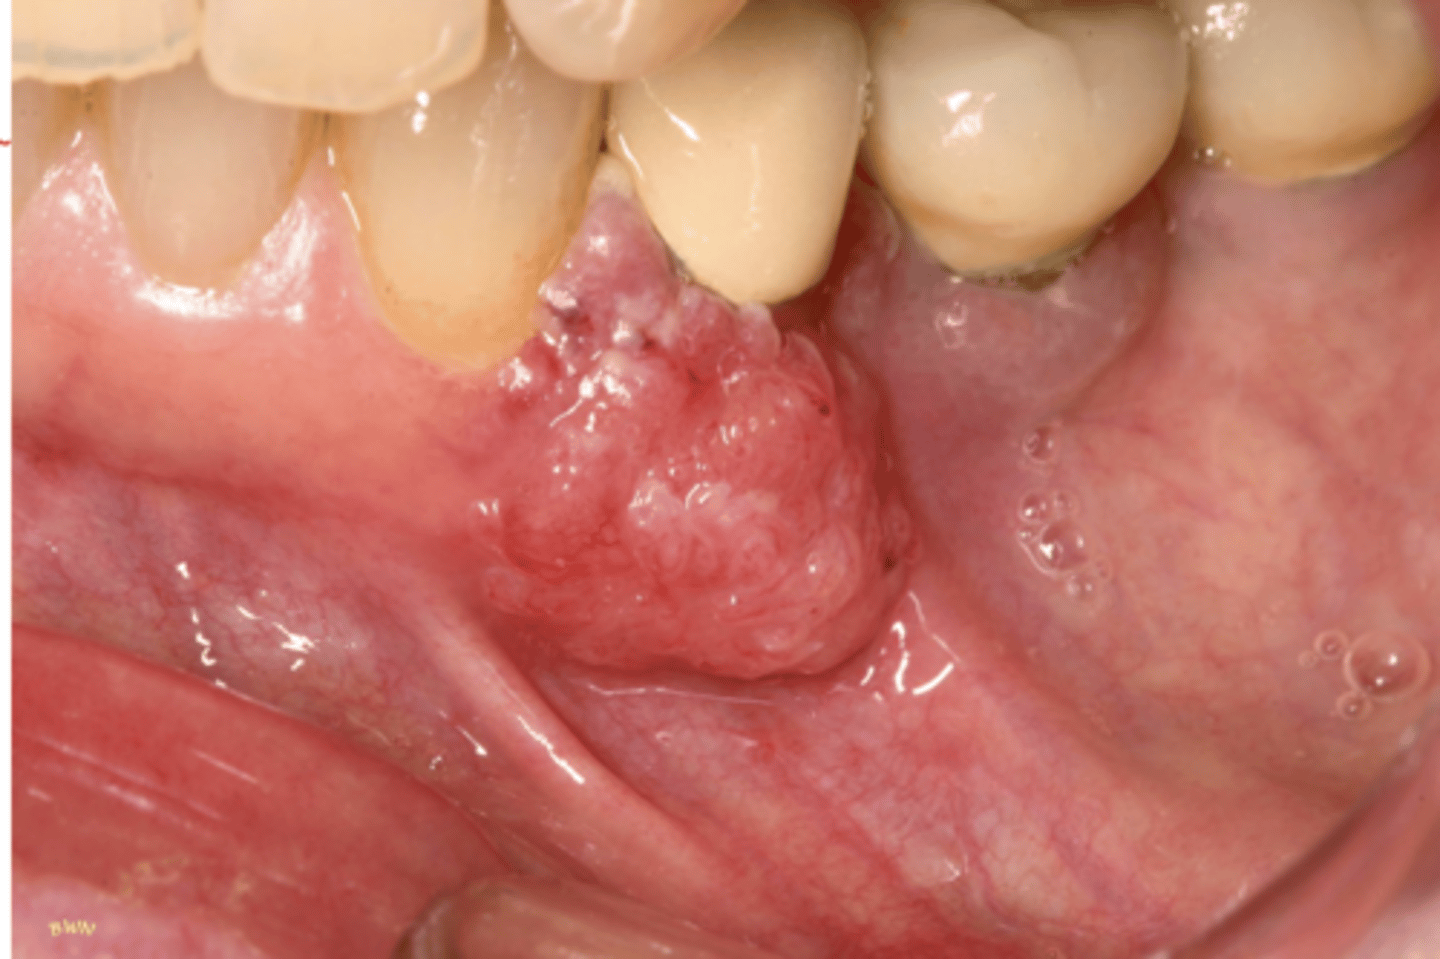

Squamous Cell Carcinoma

Hint: Varied clinical presentation